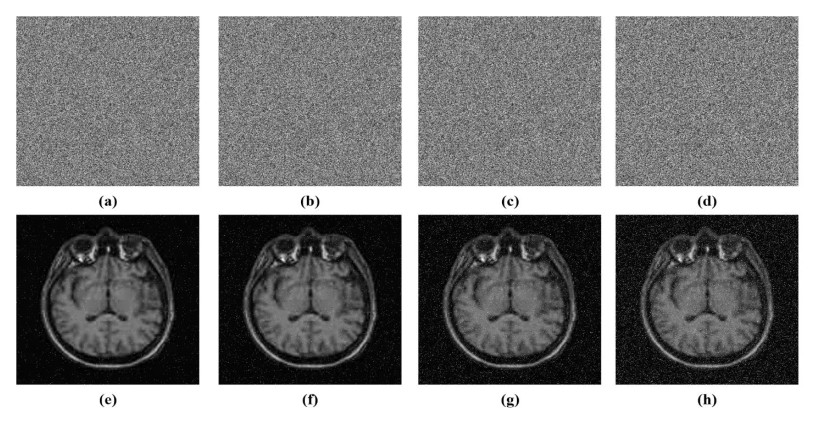

• Safeguarding medical images against unauthorized access and alteration during storage and transmission is a critical challenge in modern telemedicine systems. This paper introduces a robust method to encrypt medical images in which the confusion stage is driven by a four-dimensional (4D) fractional-order chaotic system, and the diffusion process utilizes a symmetric matrix integrated with a one-dimensional (1D) chaotic map. The fractional 4D chaotic system reveals intricate dynamic behavior and is extremely sensitive to initial conditions, which enhances the confusion capability by thoroughly scrambling pixel positions. The symmetry matrix is combined with a generated chaotic sequence from a 1D chaotic map during the diffusion process that ensures strong pixel intensity diffusion and key dependence. Numerous experiments carried out on a variety of medical images confirm the outstanding performance of the suggested method. The suggested method features a key space exceeding 2100, exhibiting significant robustness to brute-force attacks. It achieves unified average changing intensity (UACI) values above 33% and number of pixels change rate (NPCR) values exceeding 99.6%, confirms robustness to differential attacks, and successfully resists chosen-plaintext and known-plaintext attacks. Additionally, the low pixel correlation and uniform histograms, along with average values of information entropy of 7.9973 and 7.9993 for 256×256 and 512×512 images, respectively, demonstrate strong resilience to statistical attacks. Furthermore, robust evaluations against cropping and noise attacks demonstrate the scheme's practical security, highlighting its suitability for the safe storage and transmission of medical images in healthcare applications. Compared with related methods, the suggested method offers superior security performance.